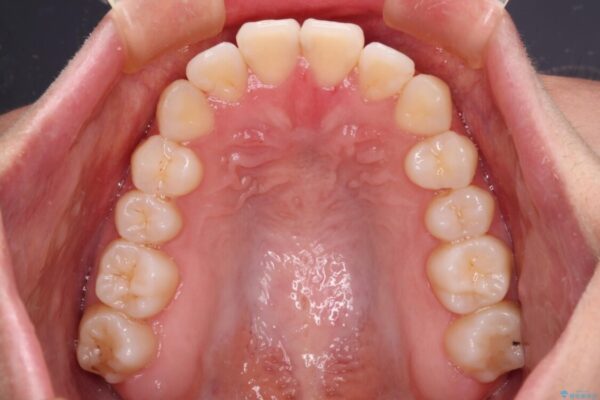

上の真ん中から2番目の歯が、他の歯よりも内側にある状態(舌側転位)だったため、インビザライン治療だけで無理に動かそうとすると歯髄壊死を起こすリスクが高いと判断。上顎前歯をワイヤー矯正で整えてから、全体をインビザライン治療で調整した事例です。

| 治療内容 | ワイヤー矯正を併用し、リスクを回避しながらのインビザライン矯正治療 |

| 概算治療費 | 950,000円(※税不明・費用は治療当時の料金) |

| 治療回数 | 10~30回 |

| 治療期間 | 1年9ヶ月 |